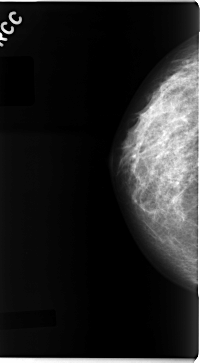

C_0090_1.RIGHT_CC

RIGHT_CC LINES 4712 PIXELS_PER_LINE 2592 BITS_PER_PIXEL 12 RESOLUTION 50 NON_OVERLAY